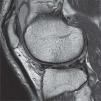

El estudio de las lesiones del cartílago tiene un importante aliado en la imagen por resonancia magnética (RM). Dadas las características propias del cartílago, su análisis preciso requiere de la obtención de imágenes por RM de alta resolución espacial, con un alto contraste y relativamente libres de artefactos1. Puesto que en los equipos de RM con campo magnético de 3.0 Teslas (T) la relación señal/ruido (RSR) intrínseca es el doble que en 1.5 T si las antenas y el sujeto son equivalentes2, 3.0 T se está convirtiendo en una herramienta cada vez más útil para el estudio del cartílago, debido a la mayor resolución y la mejor relación contraste/ruido (RCR) alcanzable (figs. 1 y 2). Esta última es especialmente significativa entre el líquido articular y las estructuras adyacentes, pudiendo incrementarse con la aplicación de supresión espectral de la grasa en secuencias ponderadas en densidad protónica (DP). Cabe señalar que, a pesar de todo lo que 3.0 T aporta de beneficioso, al trabajar con estos equipos también se ha de hacer frente a condicionantes negativos que, de no ser bien manejados, pueden tener una influencia grave en la imagen, como la mayor incidencia de los artefactos. La elección del tipo de secuencias a emplear y el ajuste correcto de los parámetros de imagen, de acuerdo con las particularidades positivas y negativas de 3.0 T, contribuye a obtener una mejora sustancial respecto a 1.5 T.